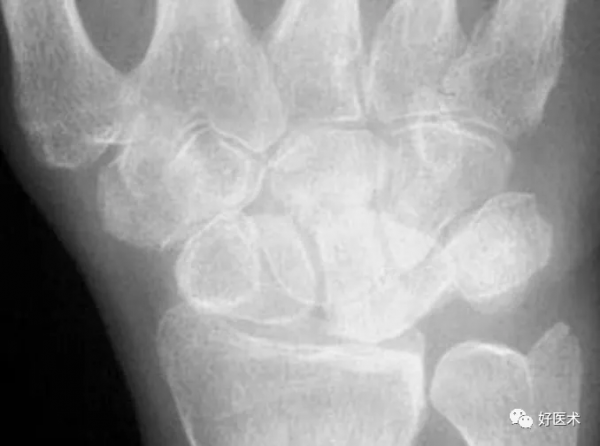

左圖:橈偏,印戒徵

右圖:屈曲

腕關節橈偏或屈曲,舟骨將會縮短、向掌側傾斜,呈印戒徵( signet ring )。